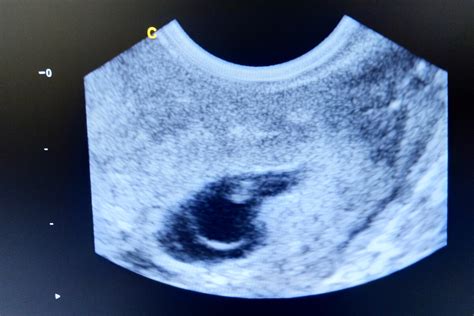

Cette semaine, vous êtes enceinte depuis 4e semaine (donc de 6 semaines d'aménorrhée), le développement de votre bébé est remarquable avec la séparation de ses doigts et de ses orteils, marquant la fin de la forme palmée Les symptômes de grossesse habituels pointent le bout de leur nez

A 4 semaines de grossesse, il est fréquent de ressentir des crampes abdominales 4 semaines de grossesse c'est un premier mois de franchi Les symptômes de grossesse habituels pointent le bout de leur nez